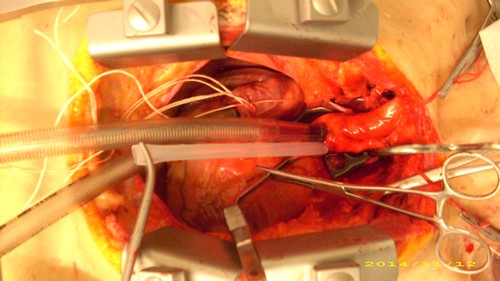

| Am

12.11. 2014 testete das Ulmer Kompetenzteam in Gegenwart von Michael

Wagner (DGAB-Vorsitzender) und Karen Conrad - welche im medizinischen

Bereich arbeitet - eine auf das Gehirn zentrierte Perfusionsmethode

mit auf 0°C gekühlter 75%iger

Vitrifikationslösung VM1 am Körper

eines vor etwa 24 Stunden Verstorbenen, der sich der medizinischen

Wissenschaft vermacht hatte. Solche Versuche sind interessant für die Testung von gerinnungs- hemmenden Mitteln und des postmortalen Verschlusses von Gefäßen, sowie die Erhaltung von überlebenden Zellen u.a. für die Alzheimer Forschung. Die Perfusion wurde nach medianer Sternotomie sowie Eröffnung und Spreizung des Thorax über eine arterielle Kanüle in der aufsteigenden Aorta und eine venöse Kanüle in der Vena cava superior als extrakorporaler Kreislauf angelegt. Durch Unterbindung der Armarterien beiderseits und Abklemmen der Bauchaorta wurde die Lösung über den Kopf geleitet. Der Kreislauf wurde von einer Rollerpumpe betrieben. Das System lief regelrecht, jedoch konnte der Rückfluss aus der oberen Hohlvene nur durch einen Wasserstrahlbetriebenen Sog erreicht werden. Ein Fluss im geschlossenen Kreislauf wurde aufgegeben, da sich so lange nach dem Ableben sehr viele Gerinnsel in der Lösung befanden. Frau Conrad schlug vor, zu versuchen ob Heparin entgegen der Theorie den Abgang der Thromben steigert (es werden immer wieder Erfahrungen in dieser Richtung diskutiert). Es wurden 35000 IE Heparin eingeführt. Es bestand der Eindruck, dass der Rückfluss sich dadurch etwas besserte. Wie zu erwarten trat eine pralle Konsistenz an Gesichtshaut und Hinterkopf auf, welche die selektive Kopf Perfusion bestätigte. Nach Entfernung der Klemmen und Kanülen wurde der Thorax verdrahtet und die Hautwunde geschlossen. Der Versuch dauerte drei Stunden. |

| Der Herzbeutel wird eröffnet. |

| Eine Kanüle wurde in die vom Herzen aufsteigende Hauptschlagader (Aorta) gelegt. Sie wird die Lösung in den Kreislauf leiten. |

| Man sieht die Kanüle in der aufsteigenen Aorta. Darunter die Kanüle in der oberen Hohlvene aus der die Lösung in den äußeren Kreislauf (extracorporaler Kreislauf) mithilfe der Pumpe zurückgeführt wird. Sie ist mit Fäden eingebunden. Die Bauchaorta ist mit einer halb verdeckten Klemme abgeklemmt. Kleine Kanülen halten die Fäden, mit denen die Armarterien unterbunden sind. Die Flüssigkeit kann nur zum Kopf (und wieder zurück) laufen. |